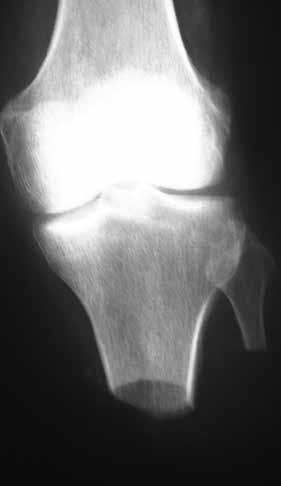

Knochen

Die Länge des Knochens ist für die Biomechanik des Stumpfes wesentlich verantwortlich. Sie richtet sich nach der Beschaffenheit der Weichteile und der Durchblutung des Unterschenkels. Vom Knochen wird prinzipiell nicht das Periost entfernt. Die Tibia wird ventral angeschrägt, so dass besonders bei kürzeren Stümpfen noch eine breite Endkontaktfläche (Spongiosa) verbleibt (Abb. 13). Im distalen Bereich (langer US-Stumpf), also im Röhrenknochenanteil, sollte man die Knochenkanten gut brechen, damit kein zusätzlicher Druck von innen gegen die dort geringen Weichteile (Haut, Sehnen) herrscht.